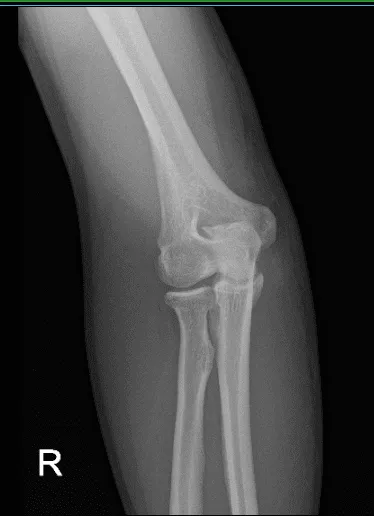

A primera vista, se sospecha que tiene una fractura de la cabeza radial. Le hicimos radiografías y descubrimos que tiene un gran osteófito del olecranon, posiblemente secundario a signos congénitos crónicos del codo.

Radiografía del codo derecho